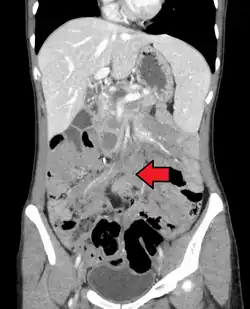

| Desmoid tumor as seen on CT scan | |